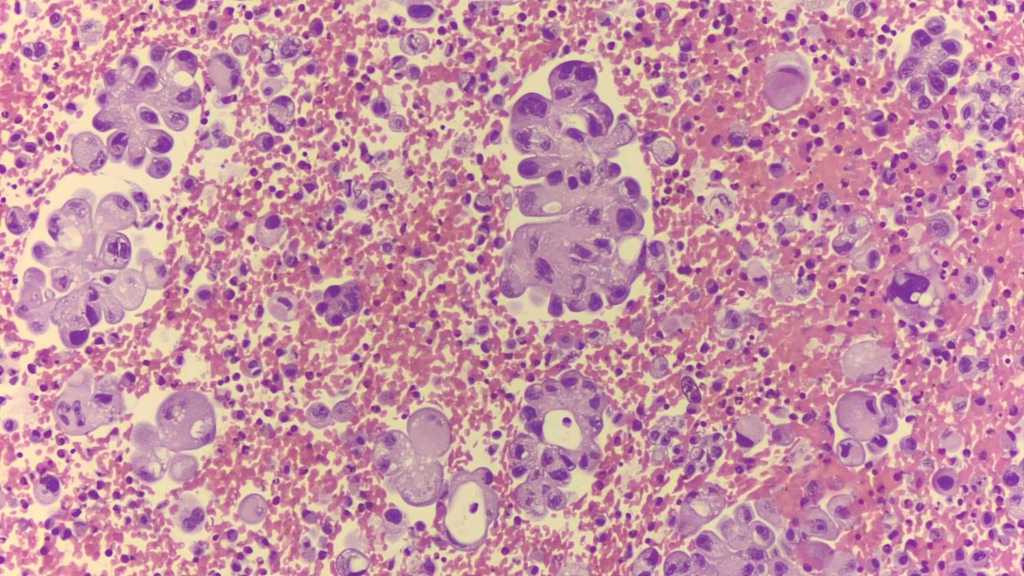

病理報告:肺癌治療真正的起點

在病理切片中,我們需要判斷:

- 是不是肺癌?

- 是腺癌(Adenocarcinoma)、鱗狀上皮癌(Squamous cell carcinoma),或小細胞癌(Small cell carcinoma)?

- 組織是否足夠做分子基因與免疫染色?

1.病理確診肺癌類型

腺癌、鱗狀上皮癌、小細胞癌等。